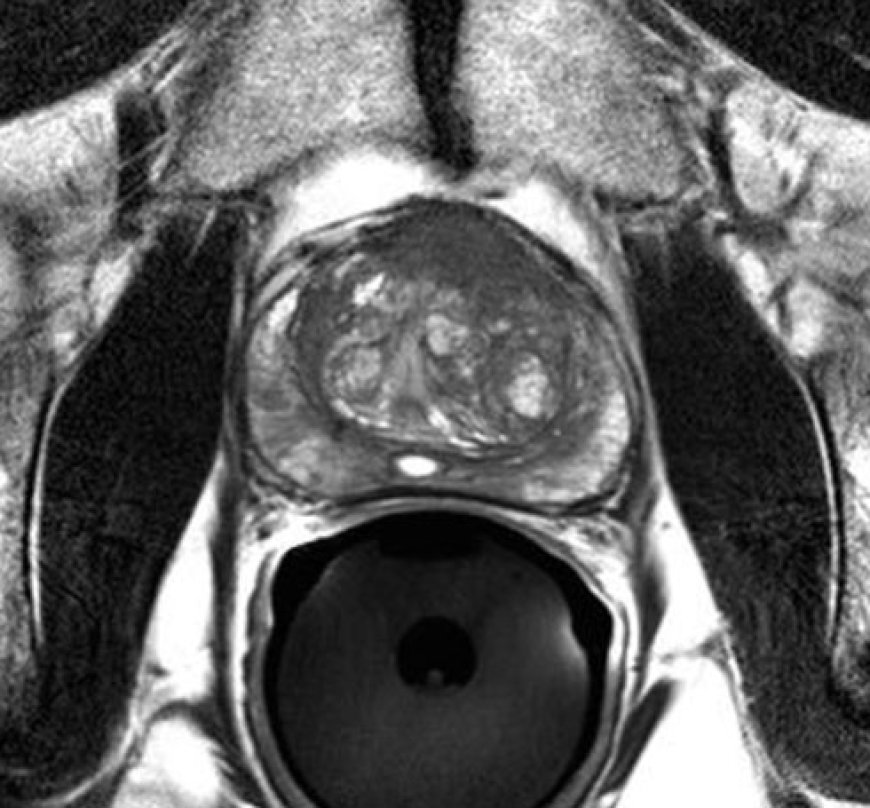

Multiparametrik Prostat MR Nedir?

Multiparametrik Prostat MR, prostatın anatomik ve fonksiyonel özelliklerini aynı anda değerlendiren gelişmiş bir görüntüleme yöntemidir. Üç farklı MR sekansı bir arada uygulanır:

Diffüzyon MR: Hücre yoğunluğunu ölçer. Kanserli dokular yoğun olduğundan düşük ADC değeri gösterir. Gleason skoru ile doğrudan ilişkilidir.

Perfüzyon MR: Doku kanlanmasını inceler. Tümörler, yeni damarlar oluşturdukları için yüksek damarlanma gösterir.

MR Spektroskopi: Hücresel düzeyde kimyasal analiz sağlar. Kanserli dokuda kolin artışı gözlenir.

PI-RADS Skorlama Sistemi

MR sonrası lezyonlar PI-RADS 1’den 5’e kadar puanlanır:

PI-RADS 1-2: Klinik olarak önemsiz

PI-RADS 3: Takip önerilir

PI-RADS 4-5: Kanser şüphesi yüksek, biyopsi önerilir

Bu sistem sayesinde, gereksiz biyopsilerin önüne geçilirken, hedefe yönelik biyopsi yapılması sağlanır.